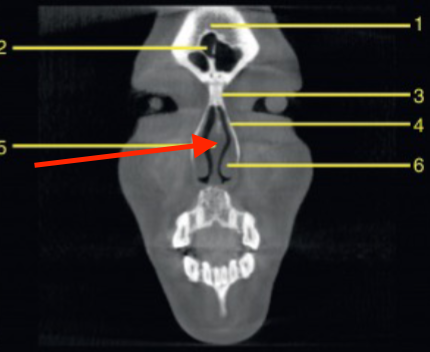

mental foramen

what is the structure indicated by the arrow

orbit

what is 6

submandibular fossa

identify 5

coronal

what plane